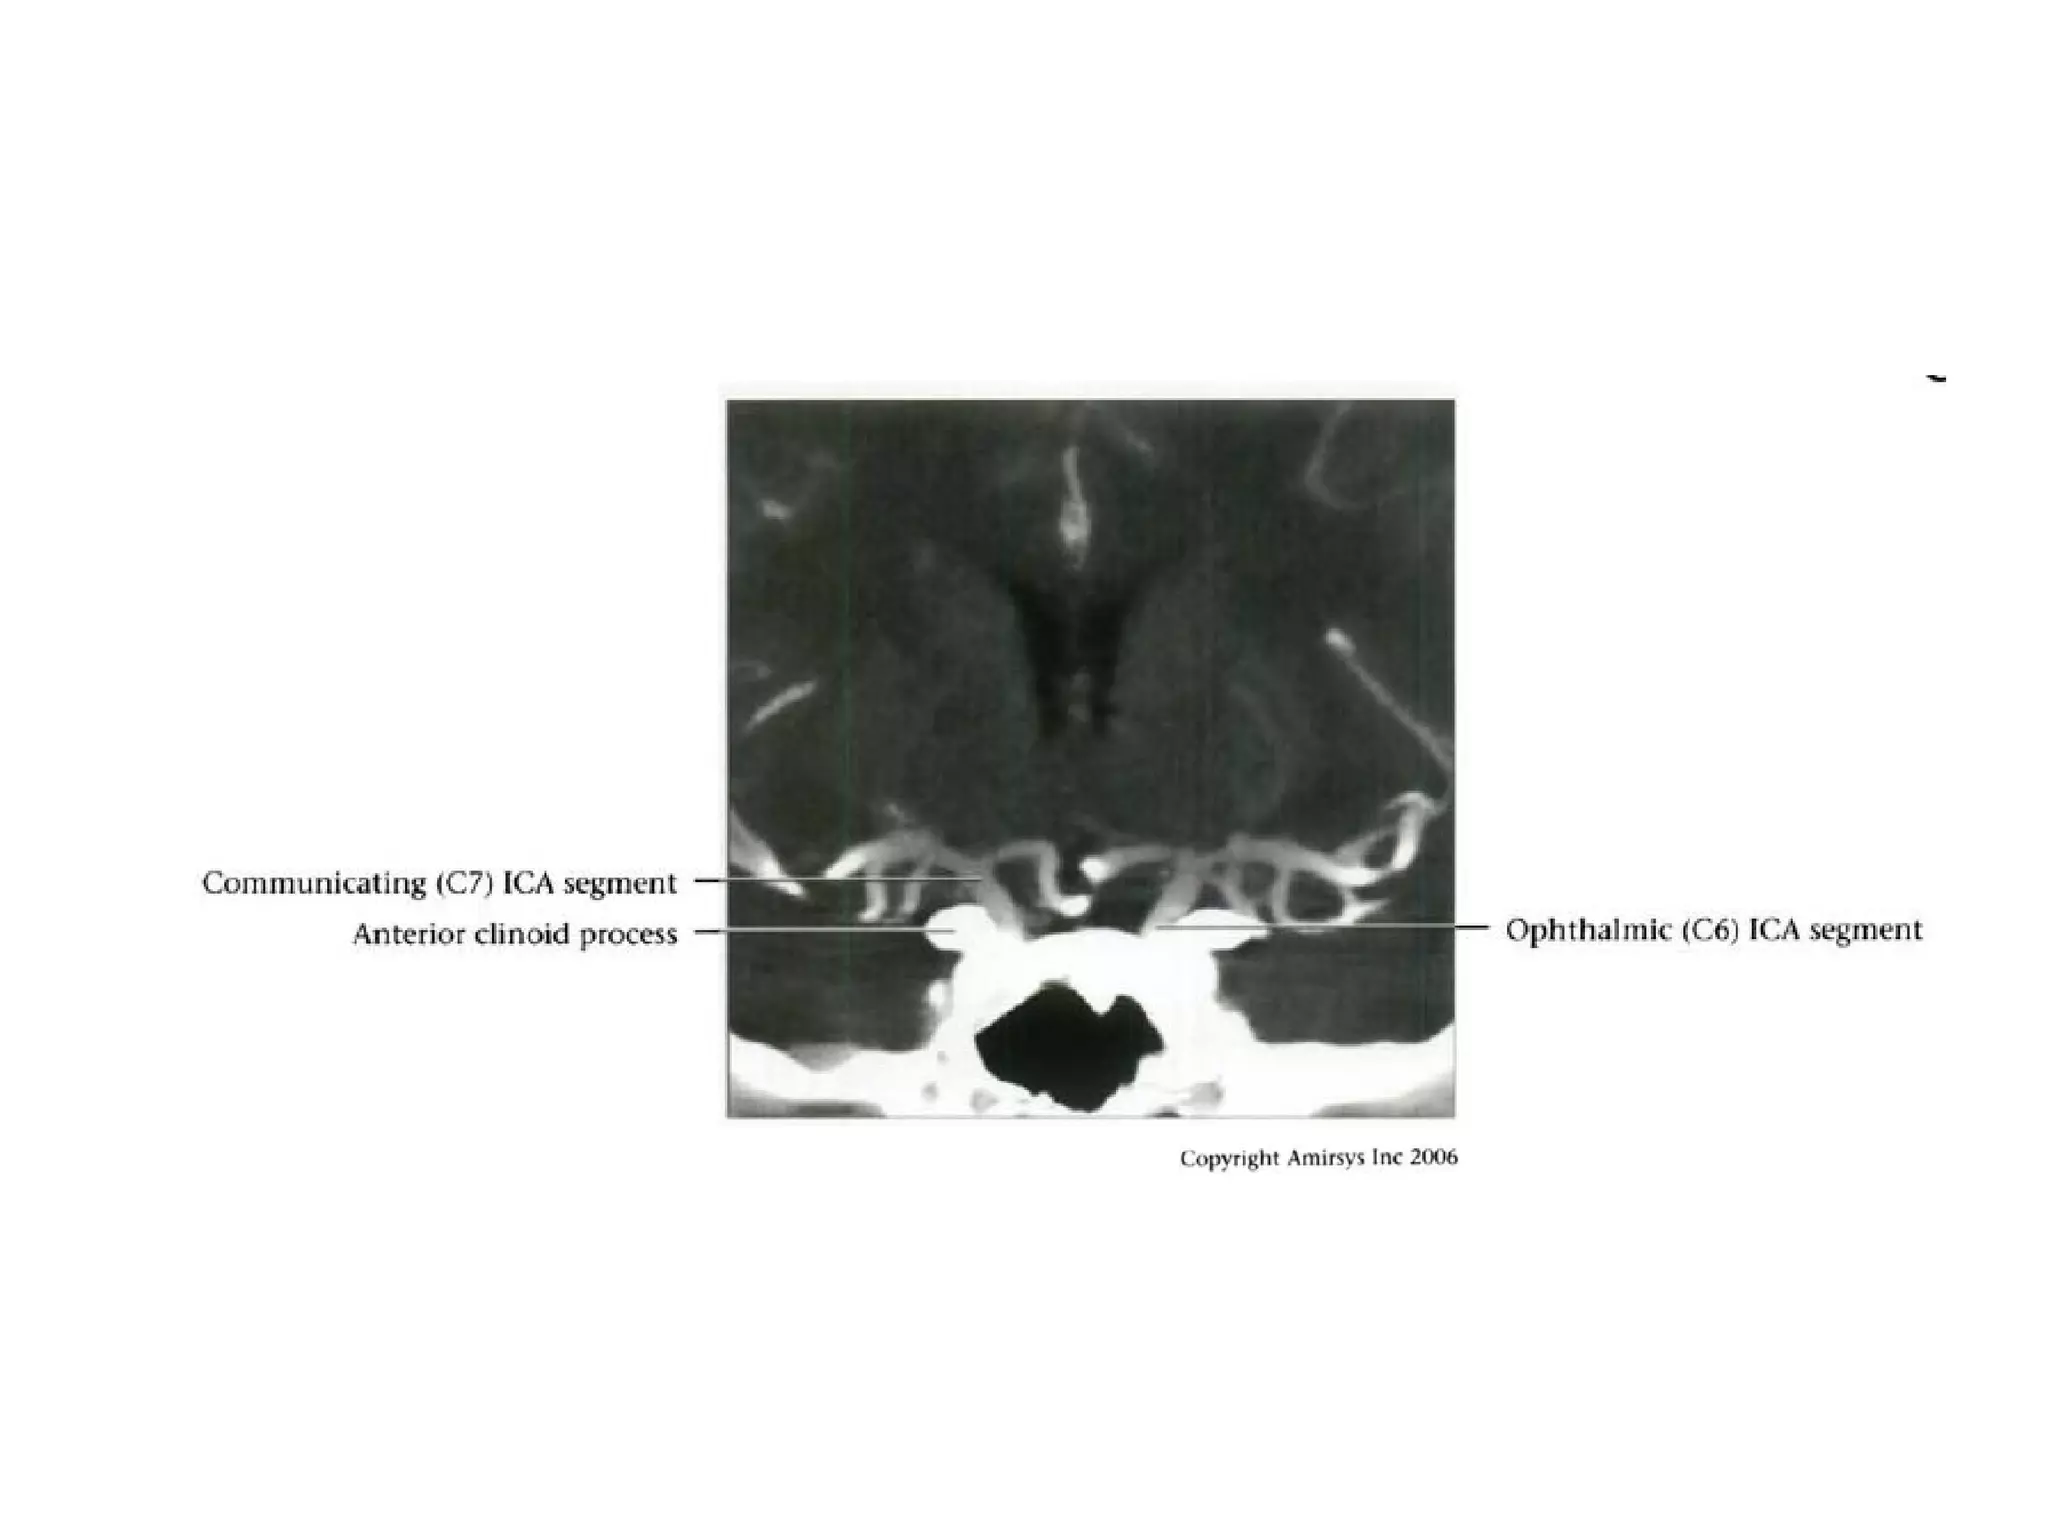

Ophthalmic (C6) segment

• Extends from distal dural ring at superior clinoid

to just below posterior communicating artery

(PCoA) origin

• Two important branches

- Ophthalmic Arteries (originates from

anterosuperior ICA, passes through optic canal

to orbit; gives off ocular, lacrimal, muscular

branches; extensive anastomoses with ECA)

- Superior hypophyseal artery (courses

posteromedially; supplies anterior pituitary,

infundibulum, optic nerve / chiasm)

Communicating (C7) segment

• Extends from below PCoA to terminal lCA bifurcation

into anterior cerebral artery (ACA), middle cerebral artery

(MCA)

• Passes between optic (CN2), oculomotor (CN3) nerves

• Major branches

- Posterior communicating artery

- Anterior choroidal artery (courses posteromedial,

then turns superolateral in suprasellar cistern; enters

temporal horn at choroidal fissure; supplies choroid

plexus, medial temporal lobe, basal ganglia,

posteroinferior internal capsule)